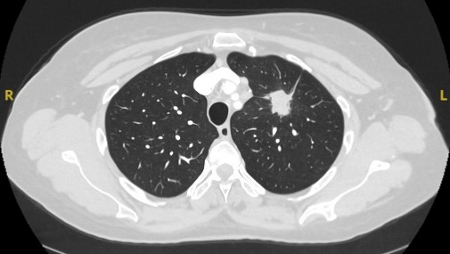

Computed tomography (CT) showing a posterior left upper lobe spiculated nodule, with ‘bronchus sign’ in a female non-smoker. Bronchoscopic forceps biopsy and brushing assisted by radial EBUS miniprobe localisation, confirmed a non-Hodgkin’s lymphoma

From the collection of Dr George Tsaknis, MD, PhD, FRCP(London), MRQA, MAcadMEd, PGCert; used with permission